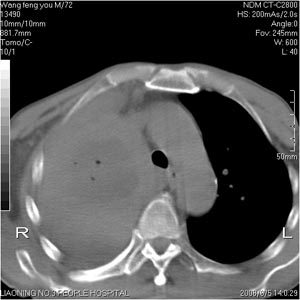

患者:男 72岁 右肩痛半年,近日来咳血,就诊.

右肺中心型肺癌并上叶不张,右侧胸腔积液,做镜检吧.

典型右中心型肺癌并右肺上叶不张,左肺转移,右胸腔积液。

考虑:右肺上叶中心型肺癌伴肺不张、肋骨转移、肩胛骨转移、右侧胸腔积液。

1.考虑:右肺上叶中央型肺癌并右肺上叶不张及右侧多发肋骨、上纵隔淋巴结及左肺转移。

2.右侧胸腔积液。

右肺上叶中心型肺癌伴肺不张、肋骨、肩胛骨、锁骨上淋巴结、右侧胸膜多发转移。